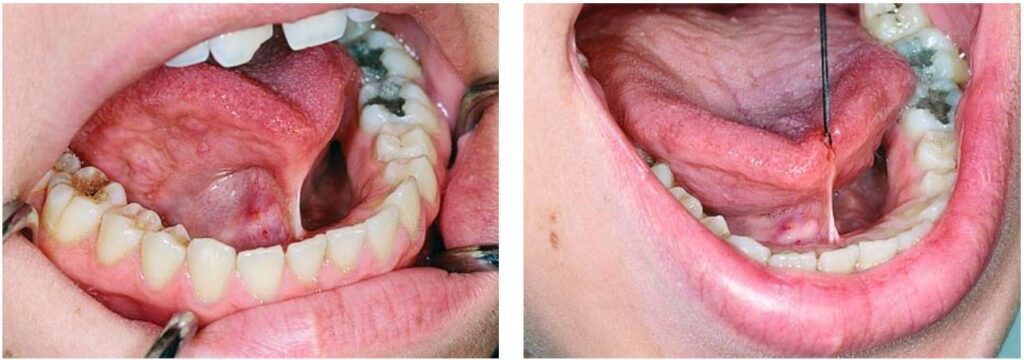

Ở hàm dưới, thắng lưỡi cũng có thể gây vấn đề, ví dụ như dính lưỡi, có thể hoàn toàn hoặc không hoàn toàn (H10.73).

Thắng lưỡi bám vào sàn miệng hoặc niêm mạc xương ổ, khi thắng lưỡi quá ngắn gây hạn chế vận động lưỡi và khó khăn trong việc phát âm.

Sau đó dùng một cây kẹp cầm máu thẳng, kẹp vào khoảng 1/3 giữa theo chiều dọc của thắng, song song với sàn miệng (H10.83).

Thực hiện rạch theo kẹp cầm máu, đầu tiên là rạch ở phía trên, sau đó đến phía dưới kẹp (H10.84, 10.85).